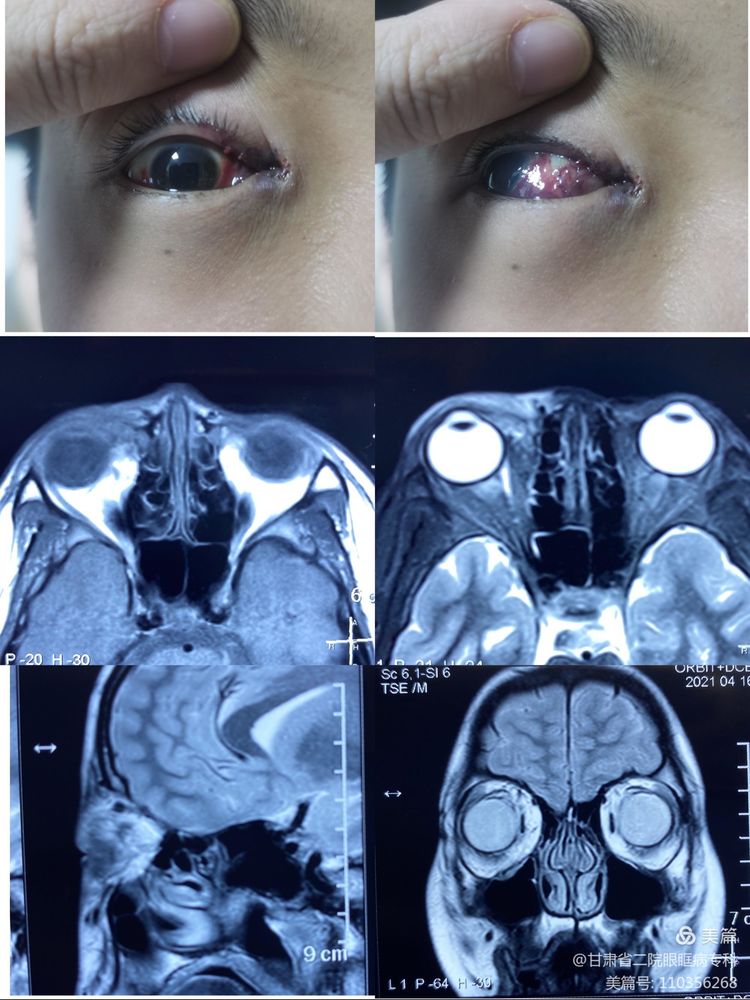

患儿男性,12岁,主因“发现右眼肿物11年”收住入院。专科查体:视力:右 1.0;左 1.2,眼压:右 20mmHg;左 12mmHg,右眼内眦部可见扩张的外观呈青紫色畸形血管,上睑内1/3无睫毛生长,睑缘可见数枚小米粒大小紫黑色赘生物,结膜下发可见迂曲扩张的畸形血管团,角膜透明,前房中深,房水清亮,KP(-),晶体透明,眼底未见异常。左眼前节及眼底未见异常。眼球突出度:右 16mm,左 14mm。入院后2021-04-16行眼眶MR平扫+增强示:右侧下眼睑占位,多考虑血管源性病变,病变由眼环前方向球旁脂肪内延伸。诊断:左侧眼睑眼眶血管畸形。

于2021-04-21在全麻下行右眼眶血管畸形硬化剂注射及切除术,术中颈部加压,采用结膜切口,分离组织暴露畸形血管,血管团内注入血管胶,畸形血管硬化后摘除,术程顺利,术后标本送病理检查。术后病理示:(右眼眶)送检组织局部血管数量增多,管壁薄厚不一,部分扩张、充血,血管瘤形成中:局部慢性炎症。